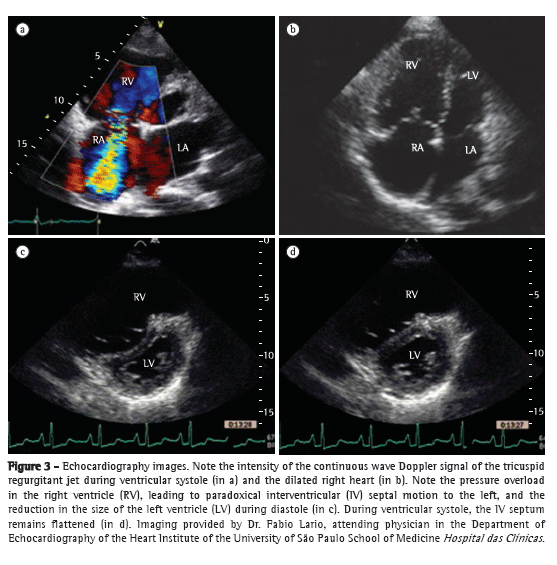

An excellent model of disease in the pulmonary microcirculation is PAH, in which vascular remodeling directly affects the distensibility properties of microcirculation. When vascular compliance is reduced, with consequent accommodation of lower volumes, the electrical impedance change in PH is likely to be decreased as well. In one study,(59) EIT was used in patients with PH for determining vascular response to vasodilator testing with epoprostenol during invasive hemodynamic assessment. Of the 8 patients evaluated, 7 did not meet the vasodilator response criteria, EIT showing no impedance change in those 7. In the lone responder, the increase in impedance change was found to correlate strongly with decreases in mPAP and pulmonary vascular resistance, regardless of the increase in systolic volume. In another study,(60) the differences in the impedance of the pulmonary circulation were analyzed in 21 patients with idiopathic PAH (IPAH) and 30 healthy subjects. The authors observed a reduction in impedance change in the IPAH group, which provides support for the use of EIT in the assessment of the pulmonary circulation and of PH.

In Brazil, a 32-electrode EIT scanner is being developed for the assessment of lung perfusion. In the context of IPAH, the images obtained with this new scanner (Figure 8) are encouraging, demonstrating not only a reduction in electrical impedance, as in the two aforementioned studies, but also a change in the impedance wave morphology, which might correlate with the pulse wave of the pulmonary circulation.